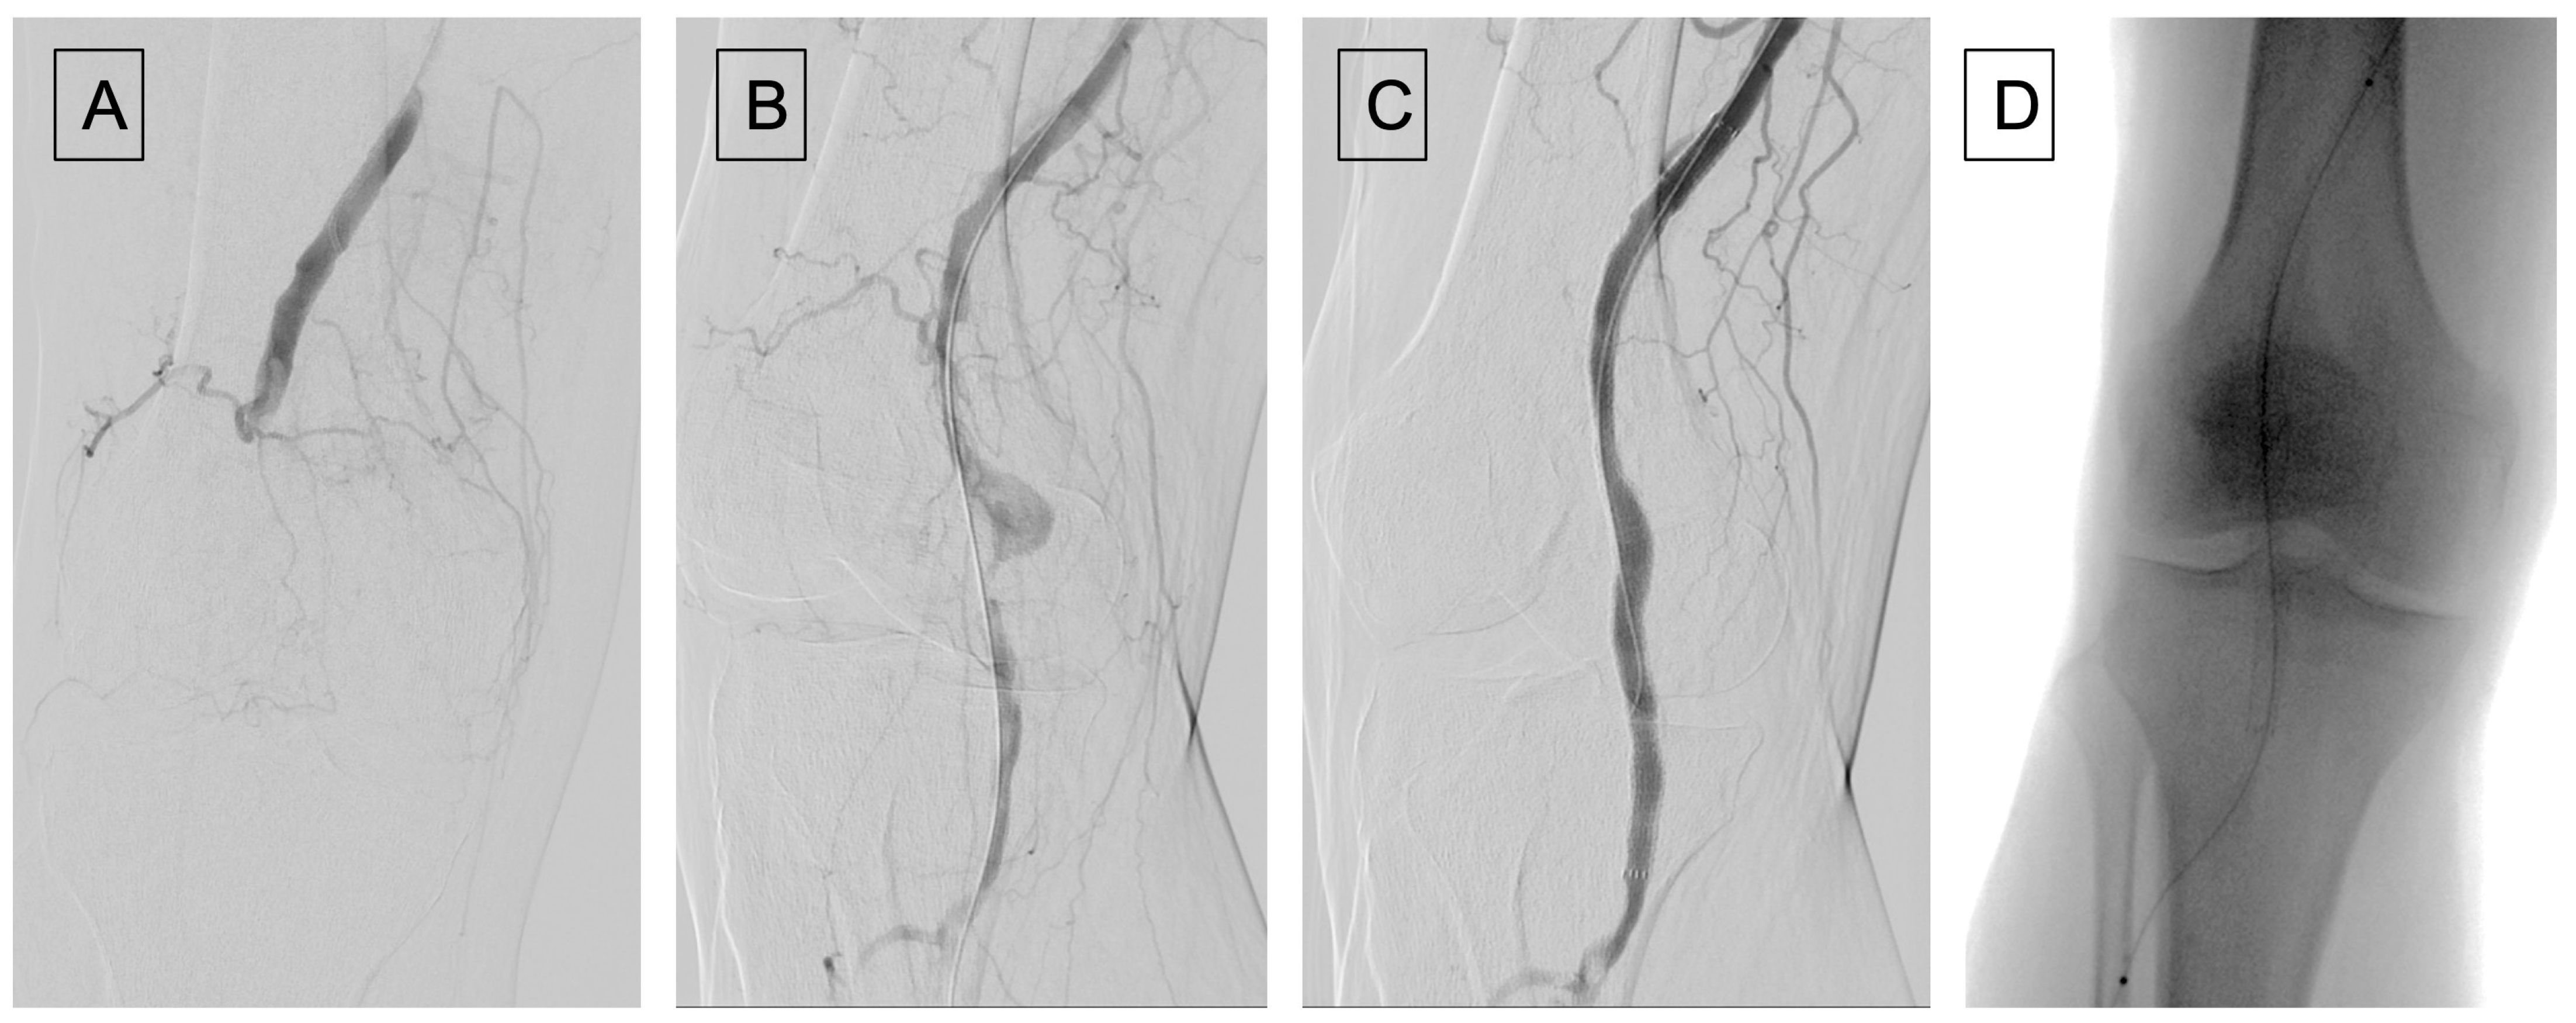

Figure 3.

(A) Ischemic foot caused by a popliteal artery thrombosis; (B) failed temptation of catheter based local thromboaspiration; (C) femoro-tibioperoneal trunk by-pass, using an inverted great safenous vein.